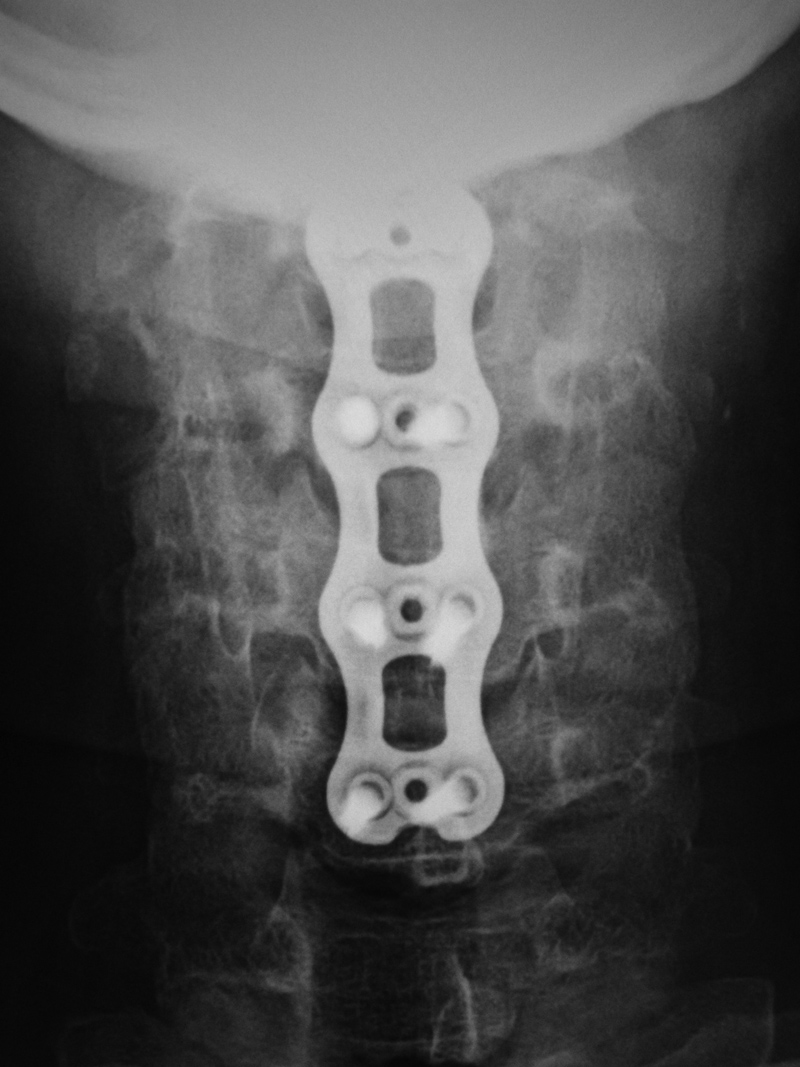

Medical Devices of the Neck and Spine an imaging guide

Cervical spinal fusion acdf 6 weeks postop xray of titanium plate and Titanium Plate Cervical Fusion Cervical plates are in use since the 1990ies for anterior cervical discectomy and fusion (acdf). The coda anterior cervical plate (acp) system was developed to enhance outcomes of anterior cervical fusion surgeries. Furthermore, achieving a precise match of the plate to the cervical spine can be challenging. To compare the biomechanical properties of a new memory compression alloy plate and. Titanium Plate Cervical Fusion.